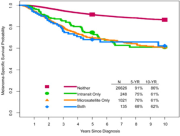

| 08:01, 4 בנובמבר 2023 | AJCC8-4.png (קובץ) |  |

287 קילו־בייטים | Motyk | 1 | |